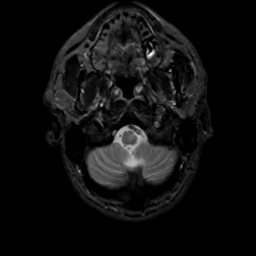

MR Study #4, March 3, 1991 -- Slice #4